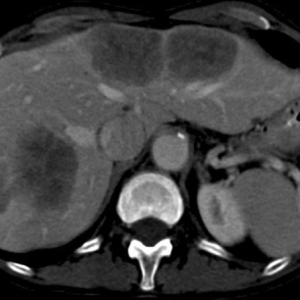

不可逆微穿孔技术治疗大肠癌肝转移一例

据报道,肠癌肝转移经完整切除后的 5 年生存率高达 58%。该手术的总体目标为达到无瘤切缘、保持门静脉及动脉流入和静脉流出、胆肠引流完整。因此,以往将无法达到阴性切缘视为手术的相对禁忌症。随着纳米刀的不可逆 ...